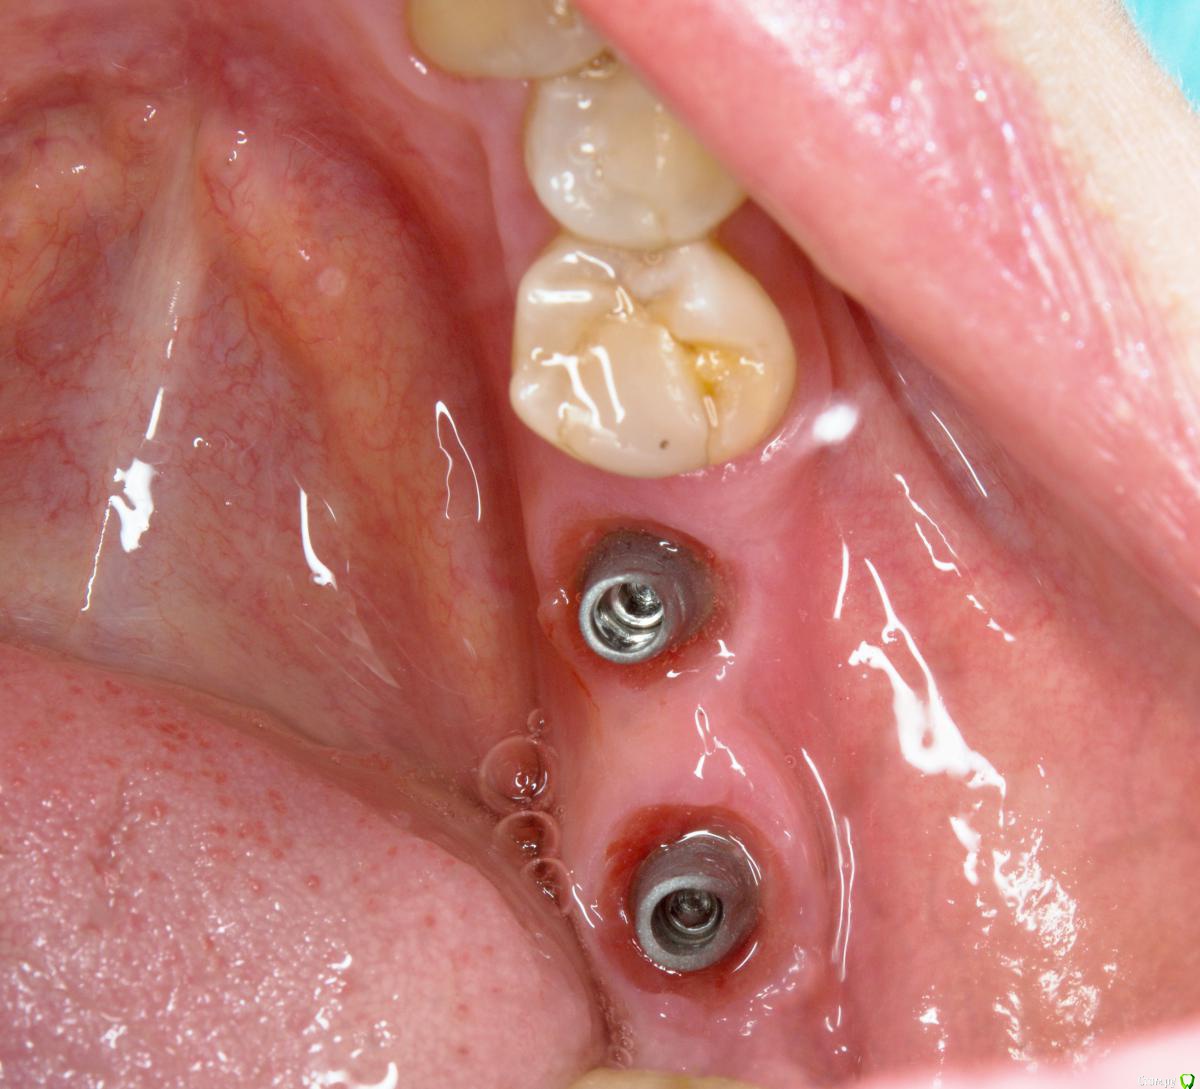

NazranDantist Опубликовано 6 сентября, 2016 Поделиться Опубликовано 6 сентября, 2016 Проведена имплантация два месяца назад, импланты SGS. Второе посещение слепок и немного модернизируем формирователи десны, третье посещение - фиксируем на готово. Дешево и сердито)). 4 Ссылка на комментарий

Evikrol Опубликовано 6 сентября, 2016 Поделиться Опубликовано 6 сентября, 2016 Почему стандартные абатменты, почему не винтовая? У вас никогда фиксирующие винты не откручивались? Ссылка на комментарий

NazranDantist Опубликовано 6 сентября, 2016 Автор Поделиться Опубликовано 6 сентября, 2016 Почему стандартные абатменты, почему не винтовая? У вас никогда фиксирующие винты не откручивались?Стандартные абатменты нравятся, а что в них плохого? Фиксирующие винты иногда откручиваются, но только на одиночных коронках. Когда протезирую одиночные импланты в боковой группе зубов, делаю винтовую фиксацию на стандартном абатменте. Ссылка на комментарий

Большой Зеленый Опубликовано 7 сентября, 2016 Поделиться Опубликовано 7 сентября, 2016 Там под десной теперь куча цемента.. Ссылка на комментарий

Большой Зеленый Опубликовано 8 сентября, 2016 Поделиться Опубликовано 8 сентября, 2016 http://forum.stom.ru/topic/26028-nemnogo-prostom-no-nadyozhnom-i-bez-vremianok/ а можно поподробнее про кучи и защемления? с учетом ссылкиКонечно. Обратите внимание ,и У меня и у Карена после слепков установлены формирователи гораздо шире чем были .И при прикручивании абатментов край уступа отлично видно.За него можно заправить фумку и после фиксации коллапс десны случается не мгновенно.Можно все вычистить.http://s017.radikal.ru/i431/1609/f3/39031174da76.jpghttp://s019.radikal.ru/i612/1609/2f/99aa85262c88.jpgПосмотрите на фото автора с абатментами .Он сам пишет."Дешево и сердито..." Ссылка на комментарий